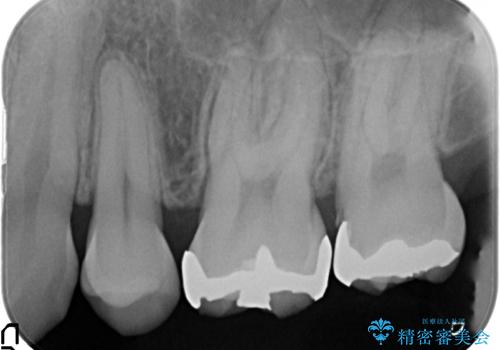

左上7近心の虫歯は歯茎より深く、歯茎を下げるため歯周外科を行いました。

歯茎より深い虫歯の治療について

虫歯が進み歯茎より深くなってしまうと、虫歯を取り残してしまうリスク、樹脂の硬化の妨げ、補綴物の不適合、歯肉炎・歯周病のリスクの増大等様々な弊害が起こり得ます。

そのため当院では歯周外科手術(歯茎を下げる手術)や歯の挺出による、虫歯が歯茎より深いという問題の解決を推奨しております。